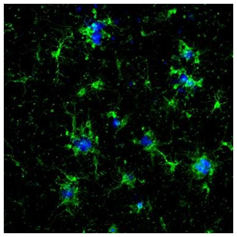

◆应用实例 1:免疫组织染色(荧光染色)

数据提供:国立长寿医疗研究中心榊原老师

样品:阿尔茨海默病模型小鼠(APPNL-G-F 小鼠)大脑新皮层冰冻切片

一抗:抗Iba1,山羊多克隆抗体(1:1,000)

二抗:Alexa Fluor488标记抗山羊IgG

Aβ染色:0.001 % FSB溶液(淀粉样蛋白染色荧光探针)

数据提供:创价大学理工学部中嶋老师

样本:大鼠(左)以及小鼠(右)大脑皮质冰冻切片

一抗:抗Iba1,山羊多克隆抗体(1:250)